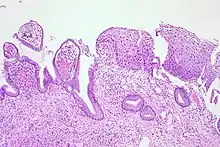

CIN is classified in grades:[17]

| Histology grade | Corresponding cytology | Description | Image |

|---|---|---|---|

| CIN 1 (Grade I) | Low-grade squamous intraepithelial lesion (LSIL) |

|

| CIN 2/3 | High-grade squamous intraepithelial lesion (HSIL) |

| CIN 2 (Grade II) |

![]() | |

| CIN 3 (Grade III) |

![]() |